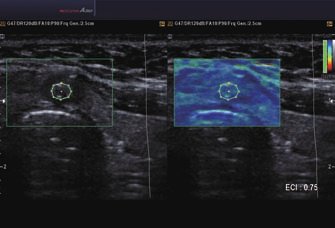

• ElastoScan™ ermöglicht eine genauere Visualisierung von Tumoren und erfasst und dokumentiert Gewebesteifheiten.

• Color Opt Flow™ bietet kraftvollere Farben und verbessert die Bildqualität.

• Mit DMR+™ kann das A30 höhere Kontraste und schärfere Kanten darstellen. Durch die Mehrfachfilterung werden Streumuster reduziert.